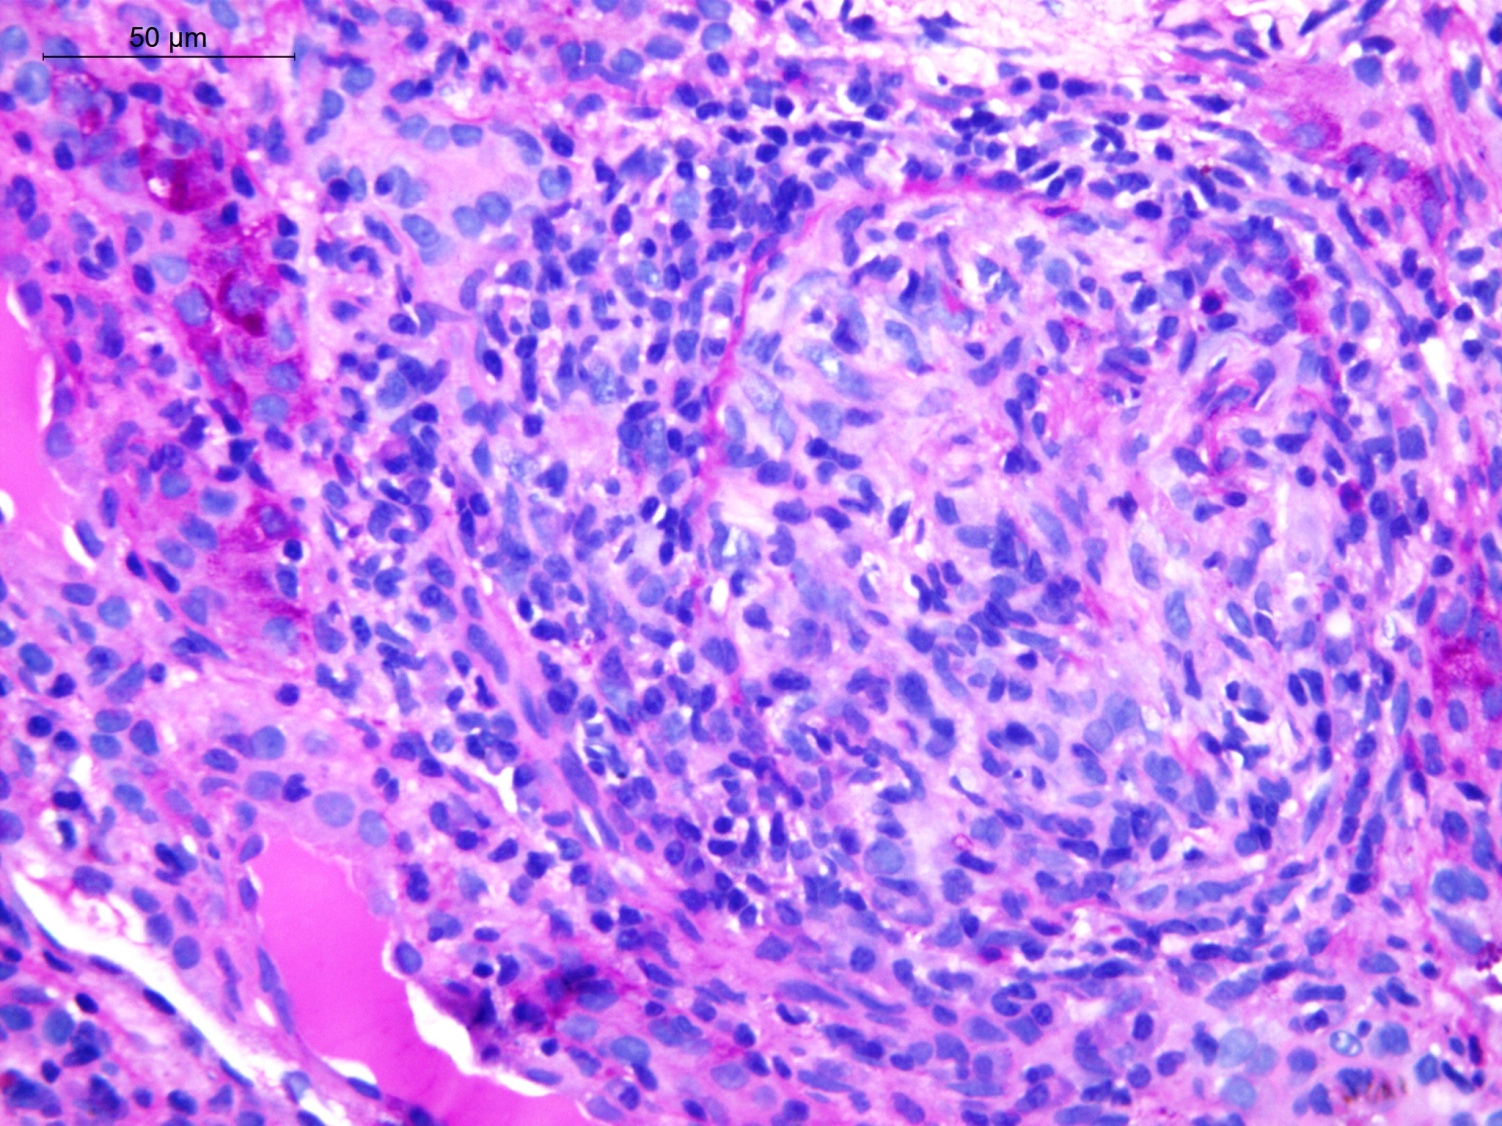

Figure 3 Blood vessels showing organised and recanalised thrombus . Tubules showing rbc casts and pus cell casts (PAS stain).

With no improvement in urine output and continued requirement for hemodialysis, decision was taken for renal biopsy 20 days after delivery, which showed acute pyelonephritis, anti-glomerular basement membrane glomerulonephritis of the crescentic variety and vascular thrombotic microangiopathy, thus making a diagnosis of Anti-GBM disease and correlating the episodes of hemoptysis, a diagnosis of the rare Goodpasture’s syndrome.